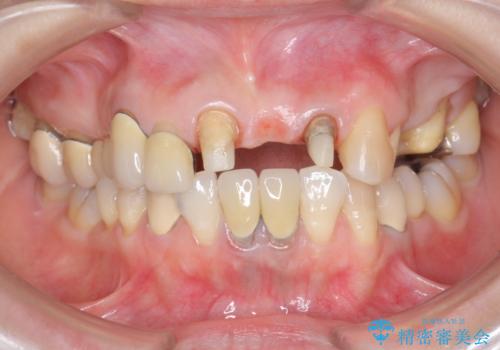

前歯ブリッジのやりかえ

- 前歯の審美障害、見た目の改善を希望され来院されました。

歯肉縁下カリエスも認められるため、挺出を行いセラミックブリッジを審美的に新製します。

- 47万円(仮歯×3・ファイバーコア×2・ジルコニアクラウン×3 歯の挺出)費用は治療当時の料金となります